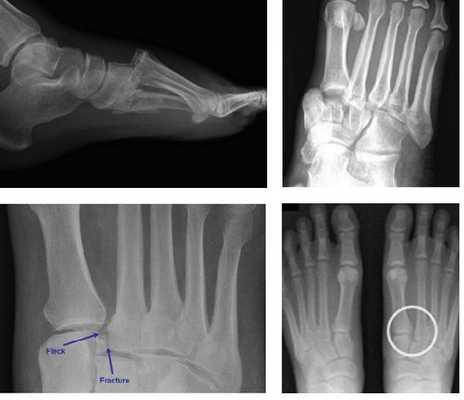

• Рентгенография в боковой проекции: смещение оснований плюсневых костей в тыльную, реже - в подошвенную сторону

(Слева) При рентгенографии среднего отдела стопы в передне-задней проекции определяется травма сустава Лисфранка без повреждения 1 -го предплюсне-плюсневого сустава. Следует отметить наличие вывихов 2-го, 3-го, 4-го и 5-го предплюсне-плюсневых суставов и множественных отрывных переломов. Кроме того, выявляется переломовывих медиального ладьевидно-клиновидного сустава.

(Справа) При рентгенографии среднего отдела стопы в передне-задней проекции определяется односторонний вывих сустава Лисфранка: все пять плюсневых костей смещены латерально. Основание пятой плюсневой кости смещено почти до уровня пяточно-кубовидного сустава. Выявляется множество костных фрагментов. (Слева) При рентгенографии среднего отдела стопы в задне передней проекции определяется дивергентный переломовывих сустава Лисфранка: 1-я плюсневая кость смещена медиально, 2-я и 3-я плюсневые кости-латерально. Кроме того, в основании 5-й плюсневой кости выявляются два поперечных перелома.

(Справа) При рентгенографии среднего отдела стопы в передне-задней проекции визуализируется редкий продольный переломовывих сустава Лисфранка. Наблюдается отделение 1-й плюсневой и клиновидной костей от оставшейся части сустава Лисфранка. Также выявляется вколоченный перелом ладьевидной кости.

(Слева) При рентгенографии среднего отдела стопы в боковой проекции визуализируется неизмененный предплюсне-плюсневый сустав. Тени оснований 1 -й и 2-й плюсневых костей накладываются друг на друга, однако остаются различимыми, поскольку 1 -я плюсневая кость намного толще, а 2-я плюсневая кость выходит за ее проксимальный контур. Дорсальный край 2-й плюсневой кости располагается на одной линии с краем промежуточной клиновидной кости.

(Справа) При рентгенографии среднего отдела стопы определяется подвывих, обусловленный повреждением связки Лисфранка. Основание 2-й плюсневой кости находится всего на 2 мм дорсальнее промежуточной клиновидной кости, однако это уже позволяет судить о повреждении связки Лисфранка. (Слева) При рентгенографии среднего отдела стопы в передне-задней проекции определяется неизмененный предплюсне-плюсневый сустав. Однако результаты исследования оказались ложноотрицательными. По причине наличия болевого синдрома пациенту была выполнена МРТ, при которой было обнаружено повреждение связки Лисфранка.

На данной рентгенограмме представлено очень серьезное повреждение стопы, возникшее следствие высокоэнергетической травмы. Результатом травмы стал вывих в суставах среднего отдела стопы).

(Слева) На рентгенограмме, выполненной без нагрузки, не видно каких-либо признаков повреждения сустава Лисфранка. (Справа) На рентгенограмме в положении стоя мы видим увеличение расстояния между костями, свидетельствующее в повреждении связок сустава Лисфранка.

При рентгенографии все снимки выполняются в сравнении со здоровой стопой. Существует несколько основных рентгенологических признаков повреждения сустава Лисфранка. 1. Отсутствие параллельности медиального края основания 2-й плюсневой и медиального края медиальной клиновидной кости 2. Расширение между основаниями 1 и 2 плюсневых костей 3. Наличие костного фрагмента в области основания 2-1 плюсневой кости 4. Тыльный подвывих на боковой проекции 5. Разрыв линии предплюсне-плюсневого сочленения.